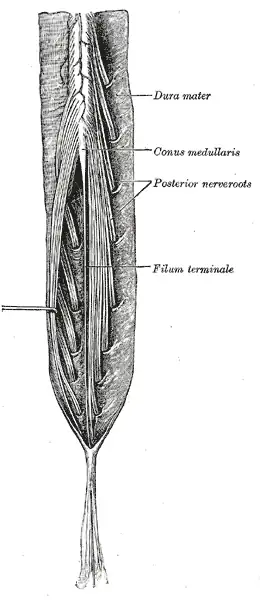

Cauda equina and filum terminale seen from behind. The dura mater has been opened and spread out, and the arachnoid has been removed. (Filum terminale (internum) labeled at center right.) | |

The filum terminale ('terminal thread') is a delicate strand of fibrous tissue, about 20 cm in length, extending inferiorly from the apex of the conus medullaris to attach onto the coccyx.[1][2] The filum terminale acts to anchor the spinal cord and spinal meninges inferiorly.[3]

The proximal/superior part – the filum terminale internum or pial part of terminal filum[3] – measures 15 cm in length and extends as far as the inferior border[1] of the second sacral vertebra (S2)[1][2] (the inferior limit sacral canal[2]). It is composed of the vestiges of neural tissue, connective tissue, and neuroglial tissue lined by pia mater.[3] It is contained within a tubular sheath of the dura mater and is surrounded by the nerves of the cauda equina (from which it can be easily recognized by its blueish-white color).[1]

The filum terminale is situated centrally[2] amid the spinal nerve roots of the cauda equina[3][2] (but is not itself a part of the cauda equina[2]).